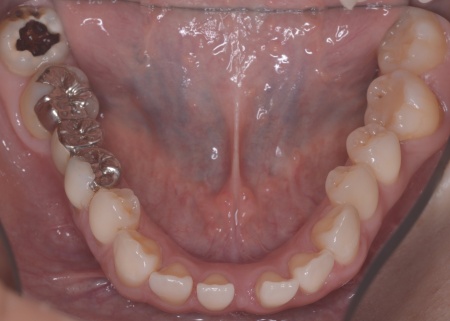

| カウンセリング | 拝見したところ、左下と右上の歯はともに大きな虫歯があり、歯だけでなく被せ物を支える土台の部分にも影響が及んでいました。

さらに、ほかの歯に入っている詰め物や被せ物の周囲にも、過去に治療した部分に再び虫歯ができる二次カリエスが複数見つかりました。 また、噛み合わせを確認したところ、奥歯で噛み合わせた際に上下の前歯が当たらず隙間ができる開咬(かいこう)が認められました。 実際に患者様の場合も、特定の歯に長期間強い力がかかり続けたことで歯や修復物の破損、さらには口腔内全体のトラブルにつながった可能性が高いと考えられました。 修復治療が必要でしたがこの噛み合わせの問題を改善しないまま行うと、治療した歯に再び過度な力が加わって被せ物の破損・脱離や虫歯の再発を招くリスクが高まります。 |